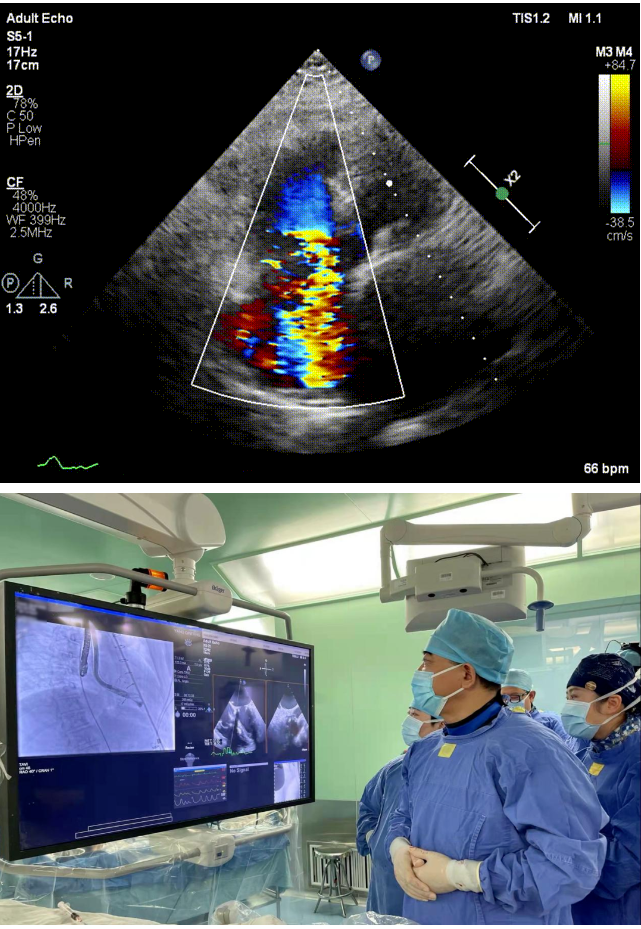

本次接受治療的患者是一名74歲的女性,14年前因風(fēng)濕性心臟病行二尖瓣生物瓣植入術(shù),合并房顫。近3年來(lái)反復(fù)因腹脹、納差、下肢水腫入院,藥物治療欠佳。心臟超聲顯示三尖瓣極重度反流(有效反流口面積:0.76cm²,反流容積:79ml),繼發(fā)性右房室增大及上、下腔靜脈增寬(右房上下徑*左右徑:52*41mm,右室左右徑:46mm,下腔靜脈:29mm),右室收縮功能正常,肺動(dòng)脈收縮壓 43mmHg,左心室射血分?jǐn)?shù)73% 。患者既往開(kāi)胸手術(shù)史,術(shù)前評(píng)估STS 評(píng)分為7.02分,CRS 9分,無(wú)法接受體外循環(huán)下三尖瓣外科手術(shù)。面對(duì)這一傳統(tǒng)治療無(wú)法解決的困境,葛均波院士及其團(tuán)隊(duì)周達(dá)新教授、潘文志教授、張?jiān)床┦俊㈥惿┦考靶某业呐舜湔浣淌凇⒗顐ソ淌诮?jīng)過(guò)討論決定,采用創(chuàng)新的Lux-Valve Plus系統(tǒng)為患者進(jìn)行經(jīng)血管三尖瓣置換。

手術(shù)在患者全麻狀態(tài)下進(jìn)行,采用經(jīng)右側(cè)頸靜脈作為入路,將裝載有人工瓣膜的輸送器緩慢推送至右心房;并在經(jīng)食道超聲和DSA的引導(dǎo)下小心調(diào)整輸送器角度,將輸送器送入右心室;逐步釋放瓣膜錨定裝置和盤(pán)片,調(diào)整瓣膜位置后,錨定瓣膜完成植入。術(shù)后右房壓明顯下降,從術(shù)前的25/10(16) mmHg降至術(shù)后即刻的12/7(10) mmHg,術(shù)后超聲提示人工三尖瓣同軸性良好,固定牢固,無(wú)反流及瓣周漏,手術(shù)室即刻拔除氣管插管。